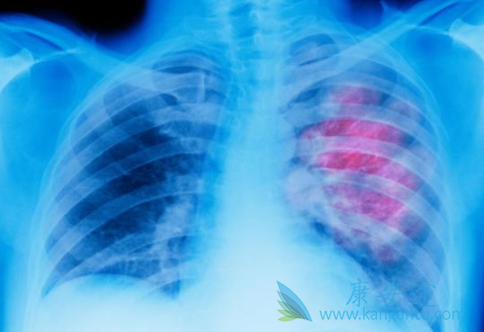

肺癌作为我国发病率和死亡率最高的癌种,每年新发的肺癌患者就高达70万左右。有一种突变类型是ROS1突变,在非小细胞肺癌的突变比例约占1%-2%,所占比例不是很大。对此类患者,克唑替尼是一线治疗的选择方案,但一段时间后患者就会出现ROS1抗性突变,导致克唑替尼耐药。研究表明,劳拉替尼在ROS1阳性晚期NSCLC患者中显示出不错的临床活性。

Lorlatinib(劳拉替尼)是辉瑞公司开发的一种新型、可逆、强效小分子ALK和ROS1抑制剂。在NSCLC中,与ALK重排相比,ROS1重排的患者中枢神经系统(CNS)转移率较低。然而,3%至53%ROS1阳性的NSCLC患者仍然会有脑转移发生的可能性。那么劳拉替尼穿透血脑屏障的能力如何呢?

最近在加拿大多伦多世界肺癌大会上,就有科学家对劳拉替尼(Lorlatinib)治疗ROS1阳性晚期非小细胞肺癌的临床数据做了报告,尤其是它对脑转移的控制情况。这是一个临床二期研究(代号EXP-6)。研究结果显示对于之前未曾使用克唑替尼和曾接受过克唑替尼治疗的ROS1阳性NSCLC患者,劳拉替尼都显示出较好的临床活性。